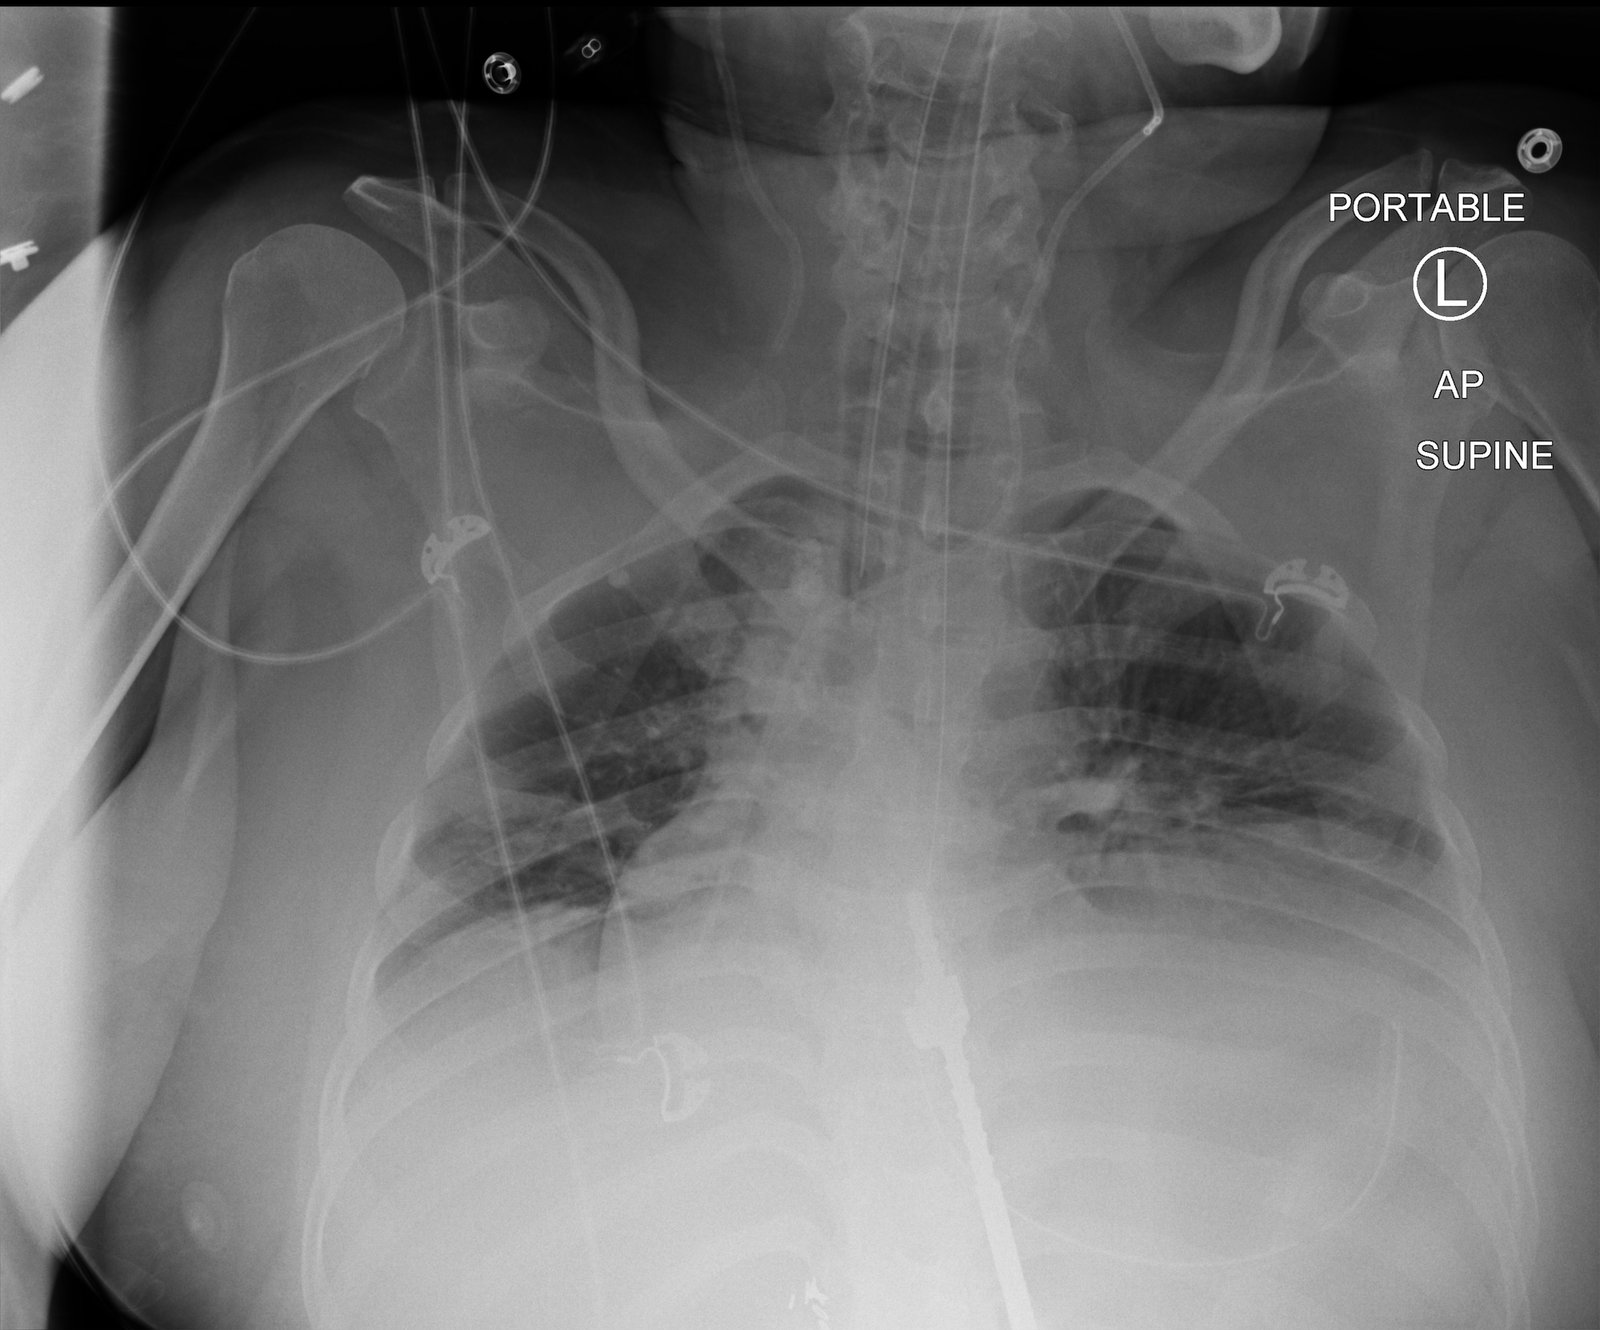

A 55-year-old female presented via transfer from a referring hospital with 48 hours of abdominal pain, vomiting and dyspnea. She was found to be in severe distress. Her temperature was 37.5°C, heart rate 130 beats per minute, respiratory rate 47 breaths per minute, blood pressure 80/48 mmHg, and oxygen saturation of 95% on a non-rebreather mask. She had distended neck veins, diminished breath sounds on the left hemi-thorax, and a distended abdomen. A chest x-ray that had been obtained at the referring hospital was immediately reviewed. The decision was made to intubate the patient. Following intubation, a nasogastric tube was placed with marked improvement in her hemodynamics. An abdomen-pelvis CT was obtained which showed a para-esophageal hernia with the majority of the stomach located in the left hemi-thorax and evidence of a bowel obstruction.

Radiography shows a dilated, gas-filled structure that fills nearly the entire left hemi-thorax. Lung markings are visible in the uppermost portion of the left hemi-thorax. There is mediastinal shift to the right. In the visualized portion of the abdomen, dilated loops of bowel are also visualized. This constellation of findings is consistent with a tension gastrothorax.